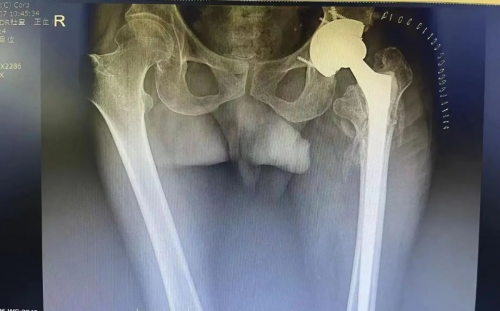

近期,患者李大爷深受“髋关节严重脱位”困扰,来到盈康一生旗下山西盈康一生总医院(运城第一医院)寻求更好地治疗。经了解得知,原来在17年前,李大爷做了髋关节置换手术,又因去年冬天摔倒,假体附近股骨骨折,就在其他医院做了翻修手术。可手术已过去一个月,李大爷只要活动,假体就会脱落。

“为什么十多年假体都没有脱落,翻修之后反而脱了?问题出在什么地方?”骨二科主任赵立新带着疑问多方查证,翻修手术医生的答复、CT检查的结果都没能给他答案。最终,他想到了3D打印技术,便立即联系医院3D打印中心,成功打印出首个立体骨科模型。

不同于普通检查的“黑白光影”,立体模型让赵立新直观看到了手术部位的三维结构,成功找到了问题根源:原来17年前没有关节联合前倾角概念,手术医生将髋臼侧假体放在了后倾角,而翻修医生通过常规检查,未看到受损部位立体结构,因此只做了股骨翻修,没有调整髋臼侧位置,导致翻修后两者不匹配使得假体脱落。

找到原因后,骨二科团队立即为李大爷精准实施了髋关节翻修术后脱位再次翻修术。手术第二天,李大爷高兴地拉着赵立新的手说:“这么多年,我从来没有这么舒服过!”该手术的成功,标志着3D打印中心在精准医疗技术方面又迈出了重要一步,骨科治疗水平再上新台阶,为更多患者带去了福音。